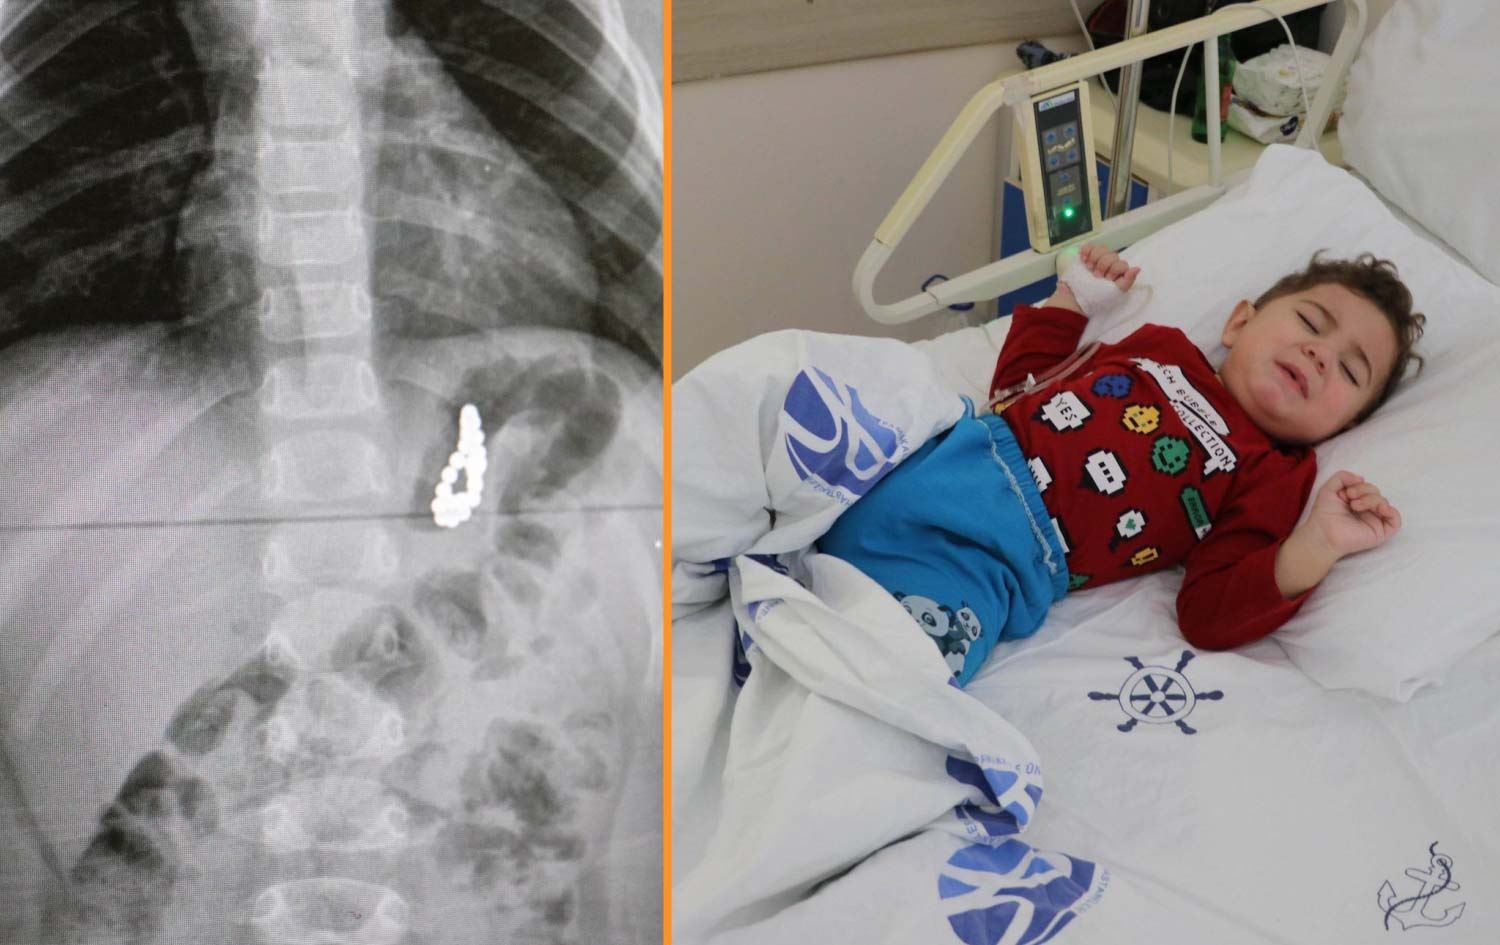

Haber Merkezi - Denizli'de 19 aylık Murat Özdemir'in midesinden, birbirine yapışık halde 17 adet mıknatıs çıkarıldı.

Pamukkale ilçesinde yaşayan Murat Özdemir adlı bebek, geçen hafta aniden rahatsızlanınca kentteki özel bir hastaneye götürüldü. Çekilen röntgende, bebeğin midesinde çok sayıda yabancı cisim bulunduğu belirlendi. Ailesinin Pamukkale Üniversitesi Hastanesi'ne götürdüğü Murat Özdemir, tedaviye alındı. Yapılan tetkikler sonucu, Murat bebeğin çok sayıda mıknatıs yuttuğu tespit edildi.

Çocuk Gastroenteroloji Öğretim Üyesi Doç. Dr. Halil Kocamaz tarafından ameliyata alınan Murat Özdemir'in midesindeki 5 milimetre boyutunda 17 adet mıknatıs operasyonla çıkarıldı. Bebeğin yuttuğu mıknatısların yapışarak bilezik şeklini aldığı ve mideyi deldiği belirlendi. Özdemir'in Pamukkale Üniversitesi Hastanesi'ndeki tedavisi devam sürüyor.